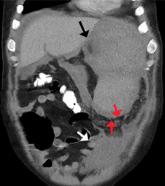

Atraumatic splenic rupture is rare but potentially life-threatening, especially if the diagnosis is delayed.